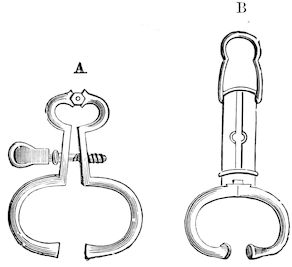

Fig. 10.—Dressing for fracture of the horn.

Symptoms. The symptoms are extremely simple. They consist mainly in the mobility of the fractured end, and such phenomena as sensitiveness, hæmorrhage, etc. When the fracture extends to the frontal bone, crepitation may also be noted.

Prognosis. The prognosis is not grave unless the fracture extends to the basilar half of the horn or affects the frontal bone.

Treatment. (1.) If the fracture is confined to the horn core, it is only necessary to bring the fragments into regular apposition, after having removed the broken end of the horn itself.

(2.) In treating a fracture affecting the middle portion of the horn or in treating animals destined for the butcher, the best method is to make a simple wound by dividing the parts with a saw below the fracture. This is a painful operation, necessitating anæsthesia, and requiring the animal to be cast or firmly fixed to a post or placed in a trevis. To diminish the painful stage of the operation, it was formerly recommended to make a circular incision extending through the entire thickness of the horn proper, and then to remove with a fine, very sharp saw the portion of the horn core. This, however, is scarcely practicable, and it is much better to make a direct section. Hæmorrhage is checked with compresses, moistened with cold water, after which a dressing known as the “Maltese cross dressing” (Fig. 10) is applied according to general principles.